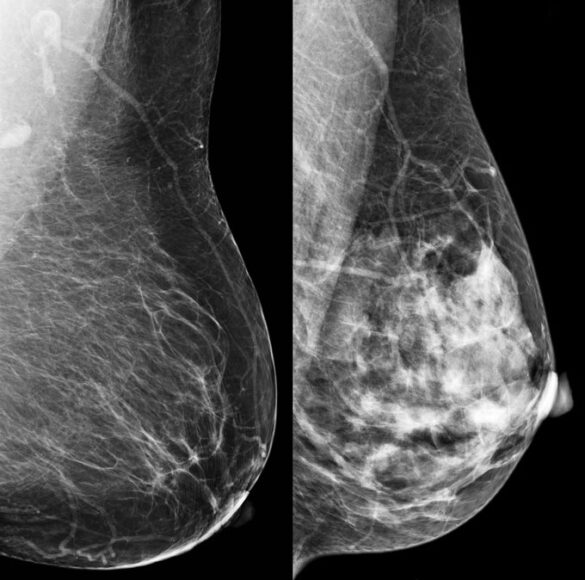

Examples of dense tissue segmentations on left MLOview (a

Examples of dense tissue segmentations on left MLOview (a What Does Fibroglandular Density Mean the levels of density are often included in a mammogram report using letters. You have low breast density, and cancer is more likely. fibroglandular density is the amount of breast tissue made up of fat vs. breast density is a measure of how much fibrous and glandular tissue (also known as fibroglandular tissue) there is in your. What Does Fibroglandular Density Mean.